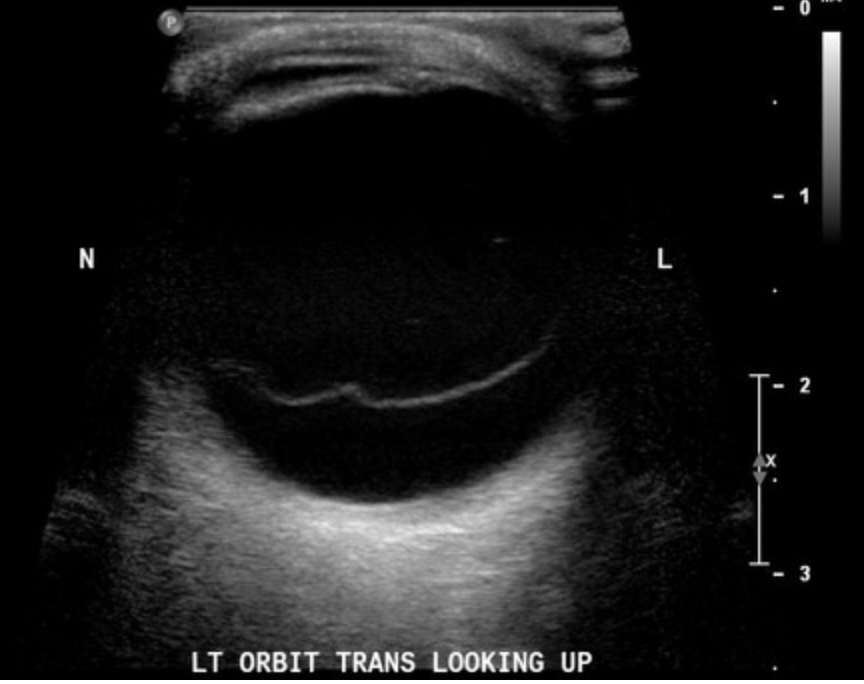

Getting the patient to move their eye side to side will accentuate the detachment and highlight its mobility

undulating retinal detachment membrane

The main DDx for retinal detachment is posterior vitreous detachment (PVD). The US in PVD also shows a hyperechoic membrane in the vitreous. However, it is usually horizontal, thin and wispy and you need high gain to visualise it well. The membrane usually crosses anterior to the optic disc.